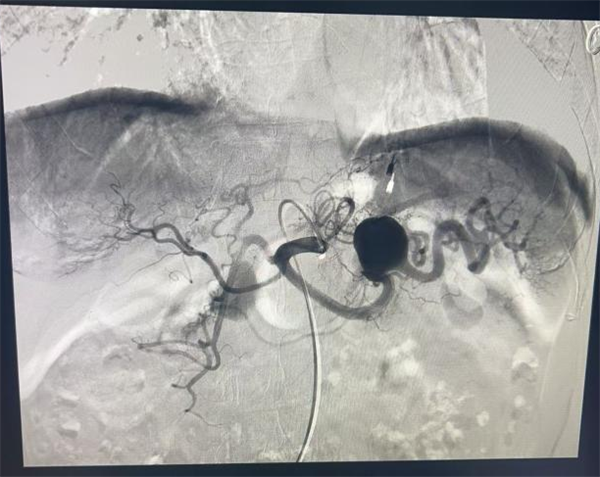

手术当天,手术团队在为患者进行局部麻醉后,熟练地穿刺患者右侧股动脉,随后将导丝和导管沿着血管缓缓送入,在精准抵达脾动脉后,通过造影清晰地显示出瘤体的形状和位置。紧接着,微导管超选择进入动脉瘤,团队成员紧密配合,迅速而精准地用弹簧圈完成了栓塞操作。

术前术后对比图